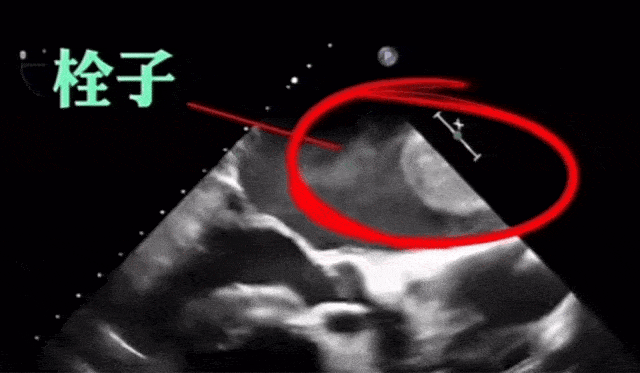

直到大人猛然刷到这张图,不说谁能知道这玩意是血栓?!这玩意就这么在身体蹦?!

这么活泼,不知道的以为是孕检图呢...

但,医学生看见直接发出尖锐爆鸣,刺激程度不亚于看“惊悚片”。

这个跳动速率不及时点救,基本人都走到快鬼门关门口了,生死簿都是闪烁状态了。

跳动的血栓,闪动的生死簿...

像这种跳动的血栓,多半是在心脏里形成的。

就是典型的心律失常引起血液流畅不通,在左心房内形成了涡流,导致心房壁内皮损伤,形成血栓。